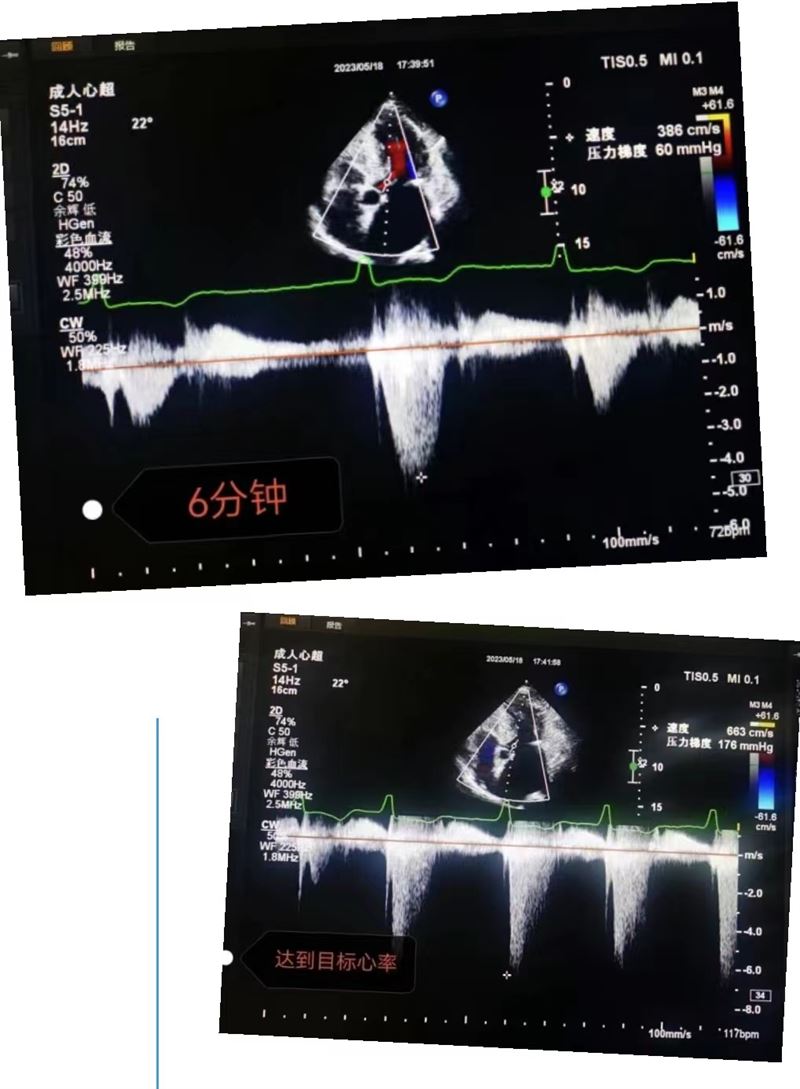

超聲科王英莉主任及心血管組賈貝主治醫(yī)師、陳輝主管護師及牛丹青護師為該患者行藥物負(fù)荷超聲心動圖。監(jiān)護儀、急救車到位,常規(guī)經(jīng)胸超聲心動圖提示室間隔增厚,左室流出道血流速度略增快,左心腔超聲造影,可清晰顯示室壁顯著增厚,符合肥厚型心肌病表現(xiàn),隨后又進行了多巴酚丁胺負(fù)荷超聲心動圖,靜息狀態(tài)下顯示左室流出道血流速度V:207cm/s,PG:17mmHg;3分鐘后心率達75次/分,左室流出道血流速度V:218cm/s,PG:19mmHg;6分鐘后心率達94次/分,左室流出道血流速度V:386cm/s,PG:60mmHg;9分鐘后達到目標(biāo)心率,左室流出道血流速度V:649cm/s,PG:169mmHg,停止用藥,藥物負(fù)荷試驗陽性,檢查過程中患者無不適癥狀,最終診斷為隱匿性肥厚型梗阻性心肌病。